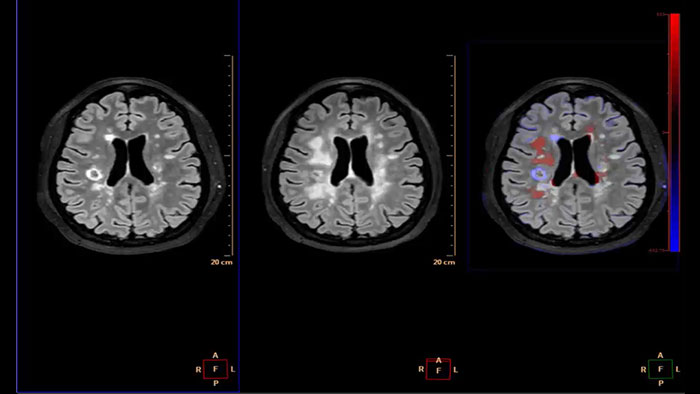

Longitudinal Brain Imaging (LoBI)

MR Longitudinal Brain Imaging (LoBI)

Gain an optimized view of the body’s most complex organ

Supports the visualization of brain images for the evaluation and monitoring of changes across multiple time points. The application performs automatic registration between studies and provides semi-automatic segmentation and editing tools for volumetric measurement of brain lesions.

• The Comparative Brain Imaging feature uses bias field-correction, intensity scaling, image registration and mathematical subtraction to provide color-coded images highlighting subtle brain changes over time.